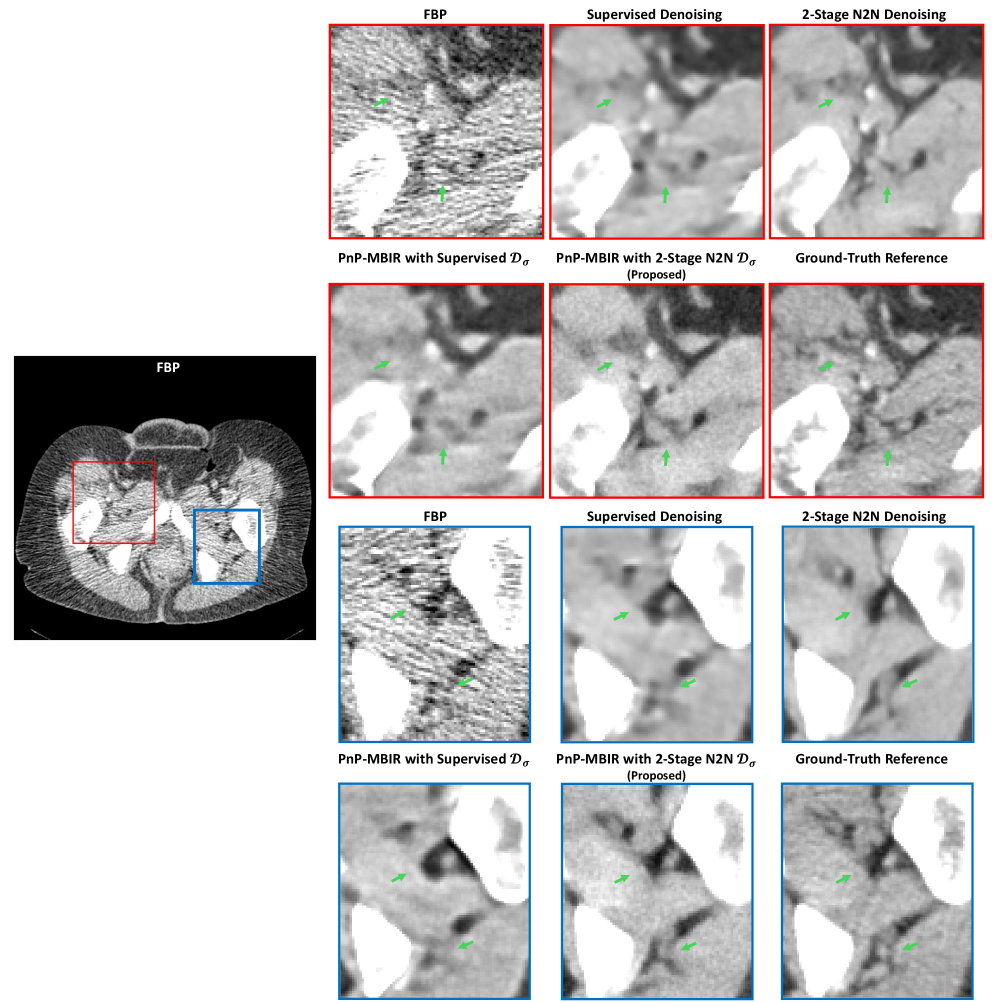

Fig. 1 qualitativly compares the reconstructions from FBP, supervised denoising, 2-stage N2N denoising, PnP-MBIR with a supervised prior, and our proposed PnP-MBIR with 2-stage (N2N) denoiser for dose-levels 100 mA, 70 mA and 40 mA respectively in the top, second and third rows. Finally a in-vivo data, acquired with 55 mA and 100 kVp, are presented in the bottom row. As expected, the low-dose FBP images (left column) are severely degraded by noise and streak artifacts. The standalone supervised denoiser (column 2) removes most of the random noise but leaves substantial structured streak artifacts and creates distortion and anomalies in the underlying anatomical structure (see blue arrows and blue boxes), since conventional supervised training framework cannot effectively learn to remove correlated streaks and noise. The standalone 2-stage N2N denoiser (column 3) further suppresses structured artifacts, but it introduces noticeable blurring and loss of fine details (see blue arrows and blue boxes). PnP reconstruction using the supervised denoiser as a prior (column 4) improves on image-domain denoising – some low-contrast features become clearer – but still leaves visible correlated artifacts in complex regions (e.g. liver, inter-tissue edges), resulting distorted reconstructions (magenta box) and loss of fine details (blue box). In contrast, the proposed PnP-MBIR reconstruction with the 2-stage N2N denoiser (column 5) yields the best visual quality: streaks and structured noise are substantially removed while high-frequency anatomical details (highlighted by blue boxes and arrows) are preserved. This output closely matches the ultra-high-dose reference (column 6) and, in practice, even exceeds it by eliminating subtle artifacts present in the ground truth reference (red arrows) due to photon starvation and attenuation in dense bone regions. A similar pattern holds in-vivo (bottom row): our method retains sharp bone edges and soft-tissue contrast (blue box and arrow) far better than other low-dose methods. In addition to noise and artifact reduction, our method maintains the subtle contrast between soft and hard bone tissues, ensuring better visualization of intra-bone structures (green boxes). Additional zoomed-in sections of the reconstructed images are provided in Appendix C for a comprehensive visual analysis.

Figs. 3–5 present zoomed-in sections from the reconstructed images obtained using different methods for qualitative evaluation. From the regions highlighted in Figs. 3–4, it is evident that our proposed PnP-MBIR reconstruction with the 2-stage N2N denoiser delivers superior visual quality. Specifically, streak artifacts and structured noise are significantly suppressed, while high-frequency anatomical details—indicated by green arrows—are well preserved. The resulting image closely approximates the ultra-high-dose reference, demonstrating the effectiveness of our approach. A similar trend is observed in the in-vivo results shown in Fig. 5 (zoomed-in red, blue, and yellow regions). Our method maintains sharp bone edges and soft-tissue contrast (blue and yellow sections) far better than competing low-dose reconstruction techniques. Beyond noise and artifact reduction, the proposed approach preserves subtle contrast between soft and hard bone tissues, enabling improved visualization of intra-bone structures (highlighted by green arrows).